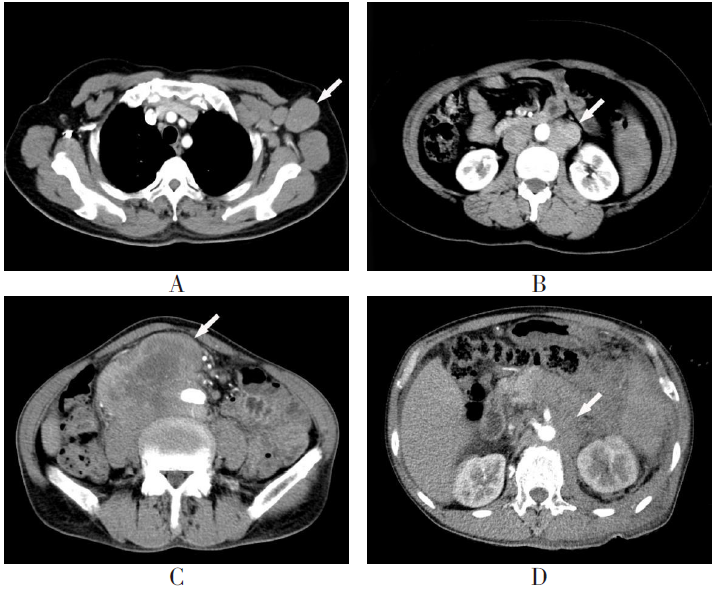

E-mail:LIU Xiaohua, HAN Tingting, GAO Yujie. The predictive value of refractory diffuse large B-cell lymphoma based on enhanced CT lymph node marginal features combined with IPI score[J]. Tianjin Medical Journal, 2026, 54(3): 303-308.